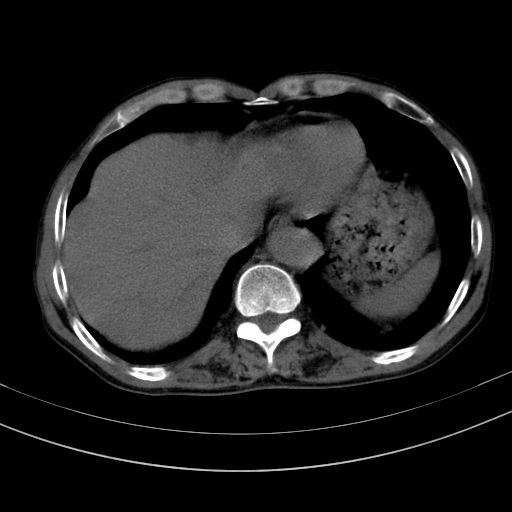

以下是引用37度在2010-1-9 14:37:00的发言:[br]1.双肾囊肿,左肾积水结石,.胆总管轻度扩张;[br]2.病灶在腹膜外,考虑纤维瘤。

以下是引用dyqct在2010-1-9 17:56:00的发言:[br]考虑:1.双肾囊肿,左肾积水结石、旋转不良。[br] 2.右侧腹直肌血肿或纤维瘤。[br]肠道准备不好。做个增强。